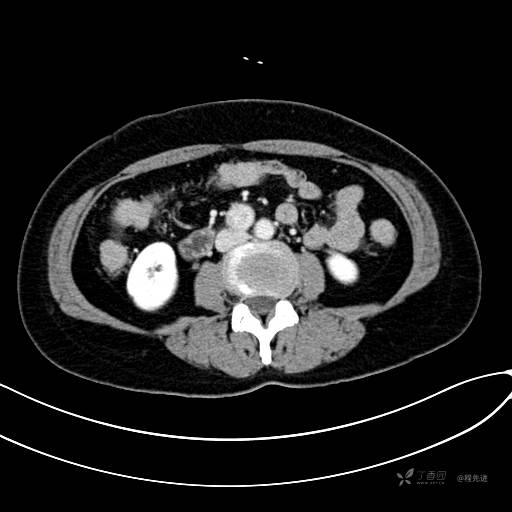

CT增强门脉期